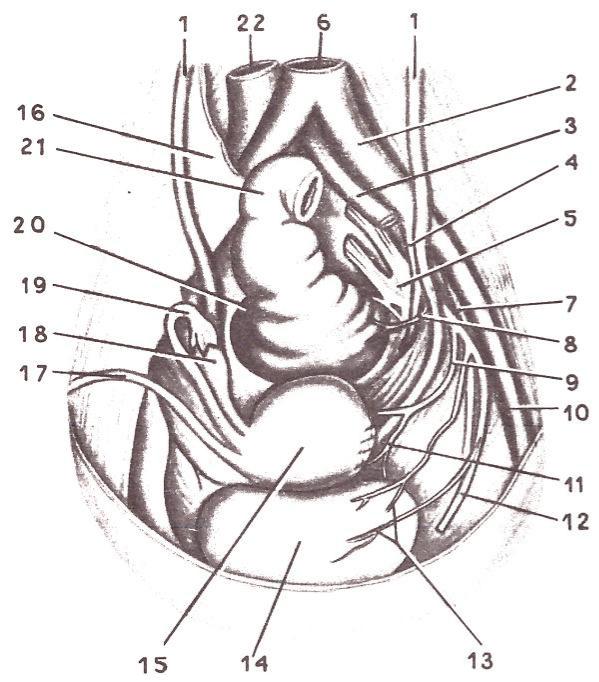

Анатомия малого таза: детальные схемы и изображения